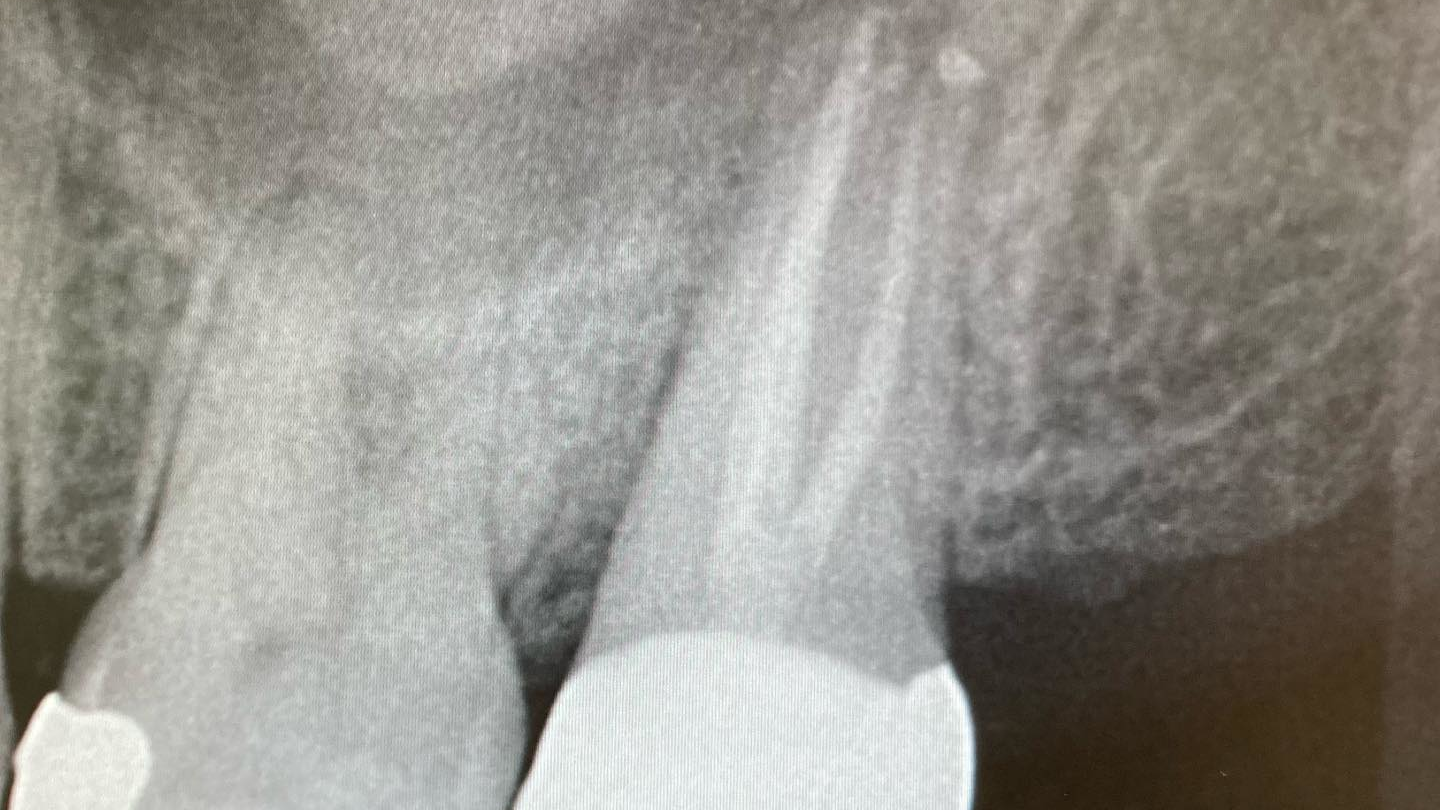

Primary

Drs. Omar Ikram and Scott Froum discuss four things that affect the waiting period between endodontic treatment and the crown procedure, as well as what can happen if you wait...